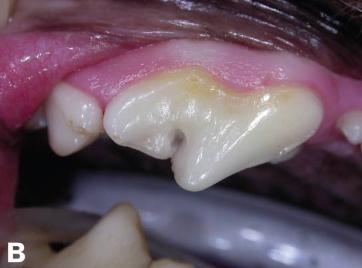

蛀牙情况修复中

而治疗方法通常是由小狗蛀牙损伤的阶段而决定,在前一、二阶段,也就是初期,兽医会将蛀牙部分的牙本质以其周围的牙釉质清除,并且杀菌后冠状物将通过汞合金填充物修复。

在第三阶段,也就是牙髓腔受损导致牙髓病,因为血液阻塞无法进入根管而导致牙齿坏死。这时候应该使用根管治疗,其包括去除坏死的牙髓组织,再进行消毒、擦洗根管,使用生物惰性材料填充根管,以及修复和密封受损的牙冠,在这阶段做这些处理能有效的防止牙龈疾病扩散到骨骼。